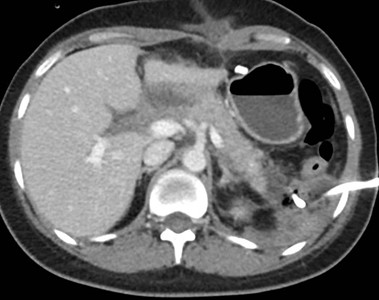

Caso 4

Paciente masculino de 35 años de edad, con antecedentes de tabaquismo, etilismo, consumo de sustancias psicoactivas. Ingresa al hospital de Sanatorio Franchin el 24 de mayo de 2024, donde se constata hipoglucemia severa con buena respuesta al glucosado hipertónico endovenoso. Al examen físico con la típica tríada de Whipple, dado por síntomas neuroglucopénicos de alteración del estado de conciencia, glucemia de 25 mg/dl y alivio sintomático después de la administración de glucosa. El paciente recupera el estado de conciencia y refiere dolor abdominal a nivel de epigastrio, por lo que se le realiza ecografía abdominal, donde se evidencia lesión nodular hipoecogénica en cuerpo del páncreas. Por esta razón se pasa al paciente a tomografía, donde se constata una formación nodular a nivel del cuerpo del páncreas, que presenta un ávido realce en fase arterial con homogeneización de la lesión en tiempo tardío.